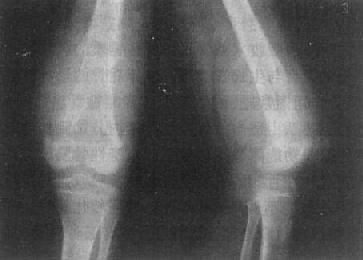

骨巨细胞瘤以20~40岁为常见,好发于四肢长骨,以股骨下端、胫骨上端和桡骨下端为常见。主要临床表现为局部疼痛、肿胀和压痛。较大肿瘤可有局部皮肤发热和静脉曲张。

长骨巨细胞瘤的X线表现多较典型(图2-1-23),常侵犯骨端,症变直达骨性关节面下。多数为偏侧性破坏,边界清楚。瘤区X线表现可有两种类型,较多的病例破坏区内可有数量不等、比较纤细的骨嵴。X线上可见似有分隔成为大小不一的小房征,称为分房型。少数病例破坏区内无骨嵴,表现为单一的骨质破坏,称为溶骨型。病变局部骨骼常呈偏侧性膨大,骨皮质变薄,肿瘤明显膨胀时,周围只留一薄层骨性包壳。肿瘤内无钙化或骨化致密影,邻近无反应性骨膜增生。边缘亦无骨硬化带,如不并发骨折也不出现骨膜增生。破坏区骨性包壳不完整,并于周围软组织中出现肿块者表示肿瘤生长活跃。肿瘤边缘出现筛孔状和虫蚀状骨破坏,骨嵴残缺紊乱。侵犯软组织出现明确肿块者,则提示为恶性骨巨细胞瘤。肿瘤一般不穿破关节软骨,但偶可发生,甚至越过关节侵犯邻近骨骼。

桡骨巨细胞瘤桡骨骨端边界清楚的骨破坏

图2-1-23 桡骨巨细胞瘤桡骨骨端边界清楚的骨破坏,

其中有多个骨隔将骨破坏区分成多个小房,病变有膨胀性